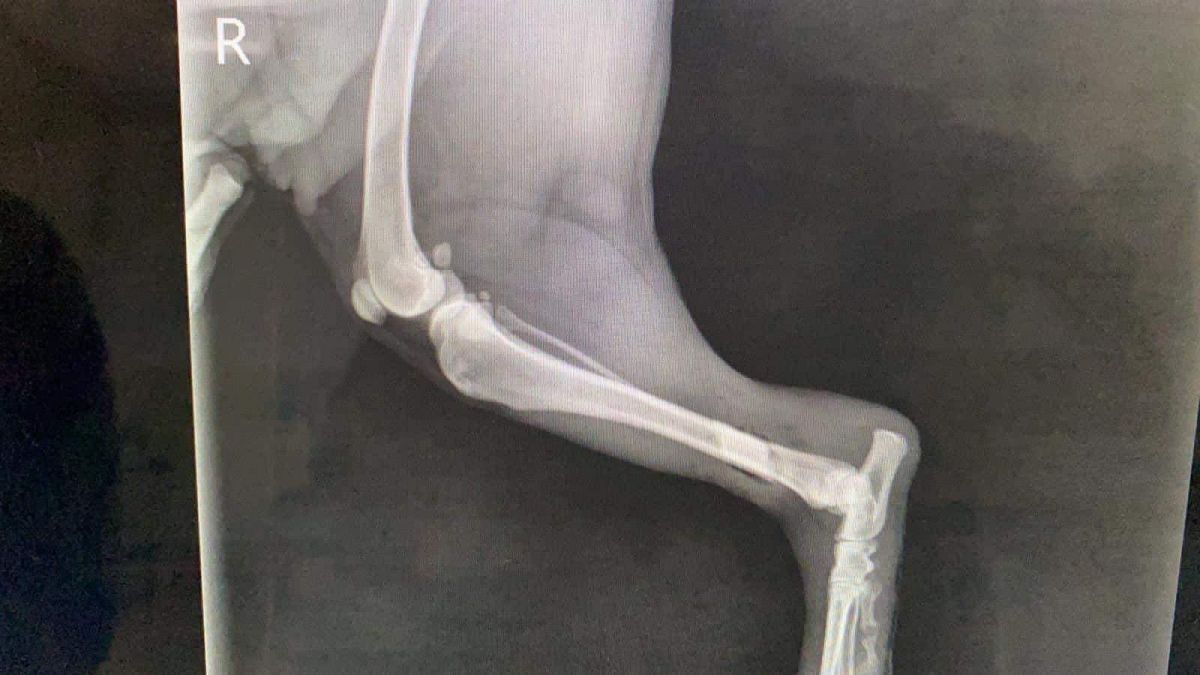

Prinsă în laț și bătută cu atâta cruzime încât i-au rupt picioarele, cățelușa a fost adusă de niște oameni miloși în cabinetul medicilor veterinari.

În urma investigațiilor și radiografiilor s-a confirmat că ambele membre posterioare prezentau fracturi duble, unul din membre cu fractura semideschisă, însă încă prezentau sensibilitate”,

Operația s-a realizat de urgență, totul a decurs bine, dar există în continuare risc de infecție, astfel că va mai rămâne internată câteva zile în clinică, recuperarea fiind una de durata.